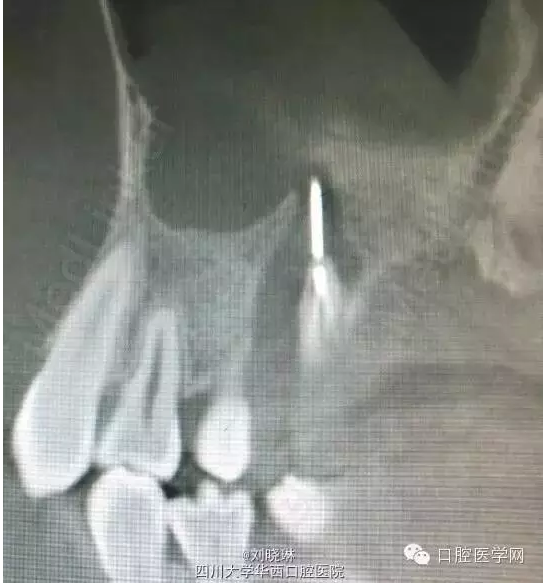

主訴:患者自訴右上后牙疼痛不適,較劇烈,自行往牙齒內插入1縫衣針,自覺疼痛有緩解,先于我院就診。

CBCT示:16牙合面大面積牙體組織密度減低影,與髓腔穿通,腭側根管內可見高密度影像,超出根尖孔外至上頜竇,根尖周組織暗影。

討論:第一次看到對自己這么狠的人,患者14歲,為年輕恒牙,根管及根尖孔粗大,也導致了縫針的進入